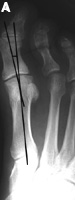

Hallux Valgus Angle

The hallux valgus angle (HAV) or hallux abductus angle is the angle formed between the longitudinal axis of the first proximal phalanx and the longitudinal axis of the first metatarsus.

Hallux VarusA.  In hallux varus or adductus the HAV is less then 5º. Normal Hallux Valgus Angle B. In normal subjects  HAV is 5º to 15º . Hallux abducto valgus is mild when HAV is 16º to 25º,Moderate Hallux Valgus C. moderate  when HAV is 26º to 35º, and severe Severe Hallux Valgus(D) when HAV is greater than 35º.